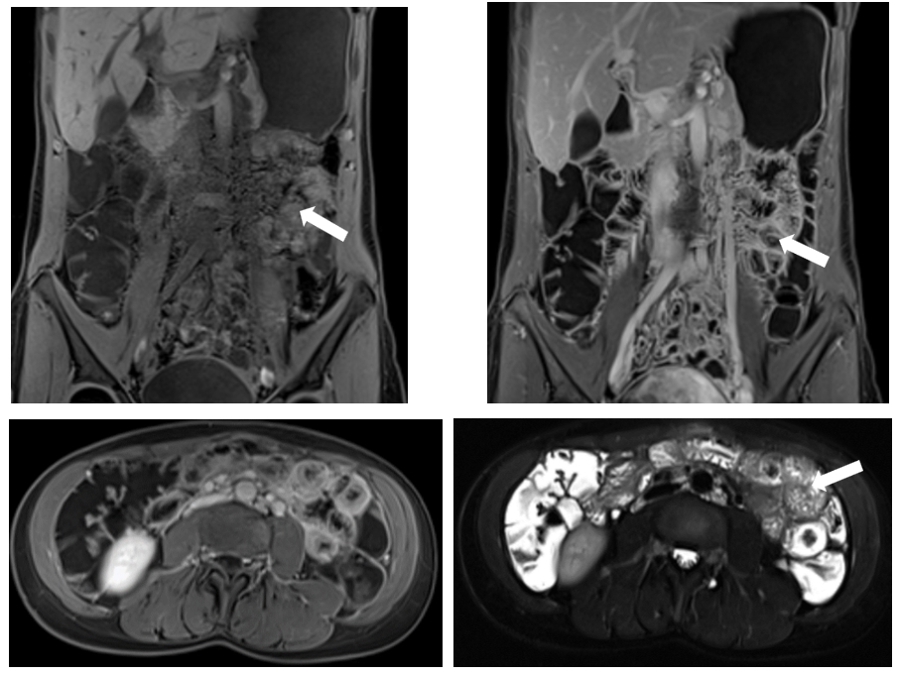

腹部-消化道MRI,肠道检查因为大FOV,对磁场均匀要求高,一直是MR成像的难点。